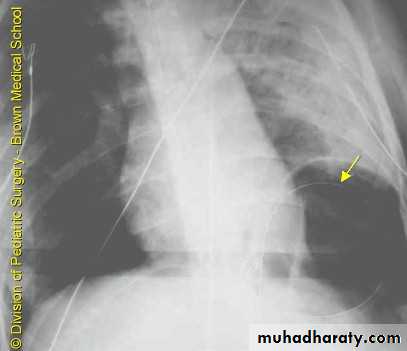

PneumothoraxX-ray pneumothorax

X-ray pneumothorax

X-ray tension pneumothorax